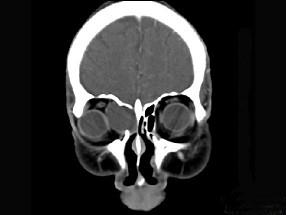

问题 女性38岁,右侧眼球运动障碍伴眼球突出4个多月,CT扫描如图,请选择正确的描述和答案 ( )

选项 A、考虑为右侧筛窦黏液囊肿 B、考虑为筛窦癌 C、囊性肿块向右侧眼眶内突入,压迫内直肌 D、右侧眶内壁呈受压变薄、断裂 E、右侧筛窦内可见囊性肿块影,边缘光整

答案 ACDE